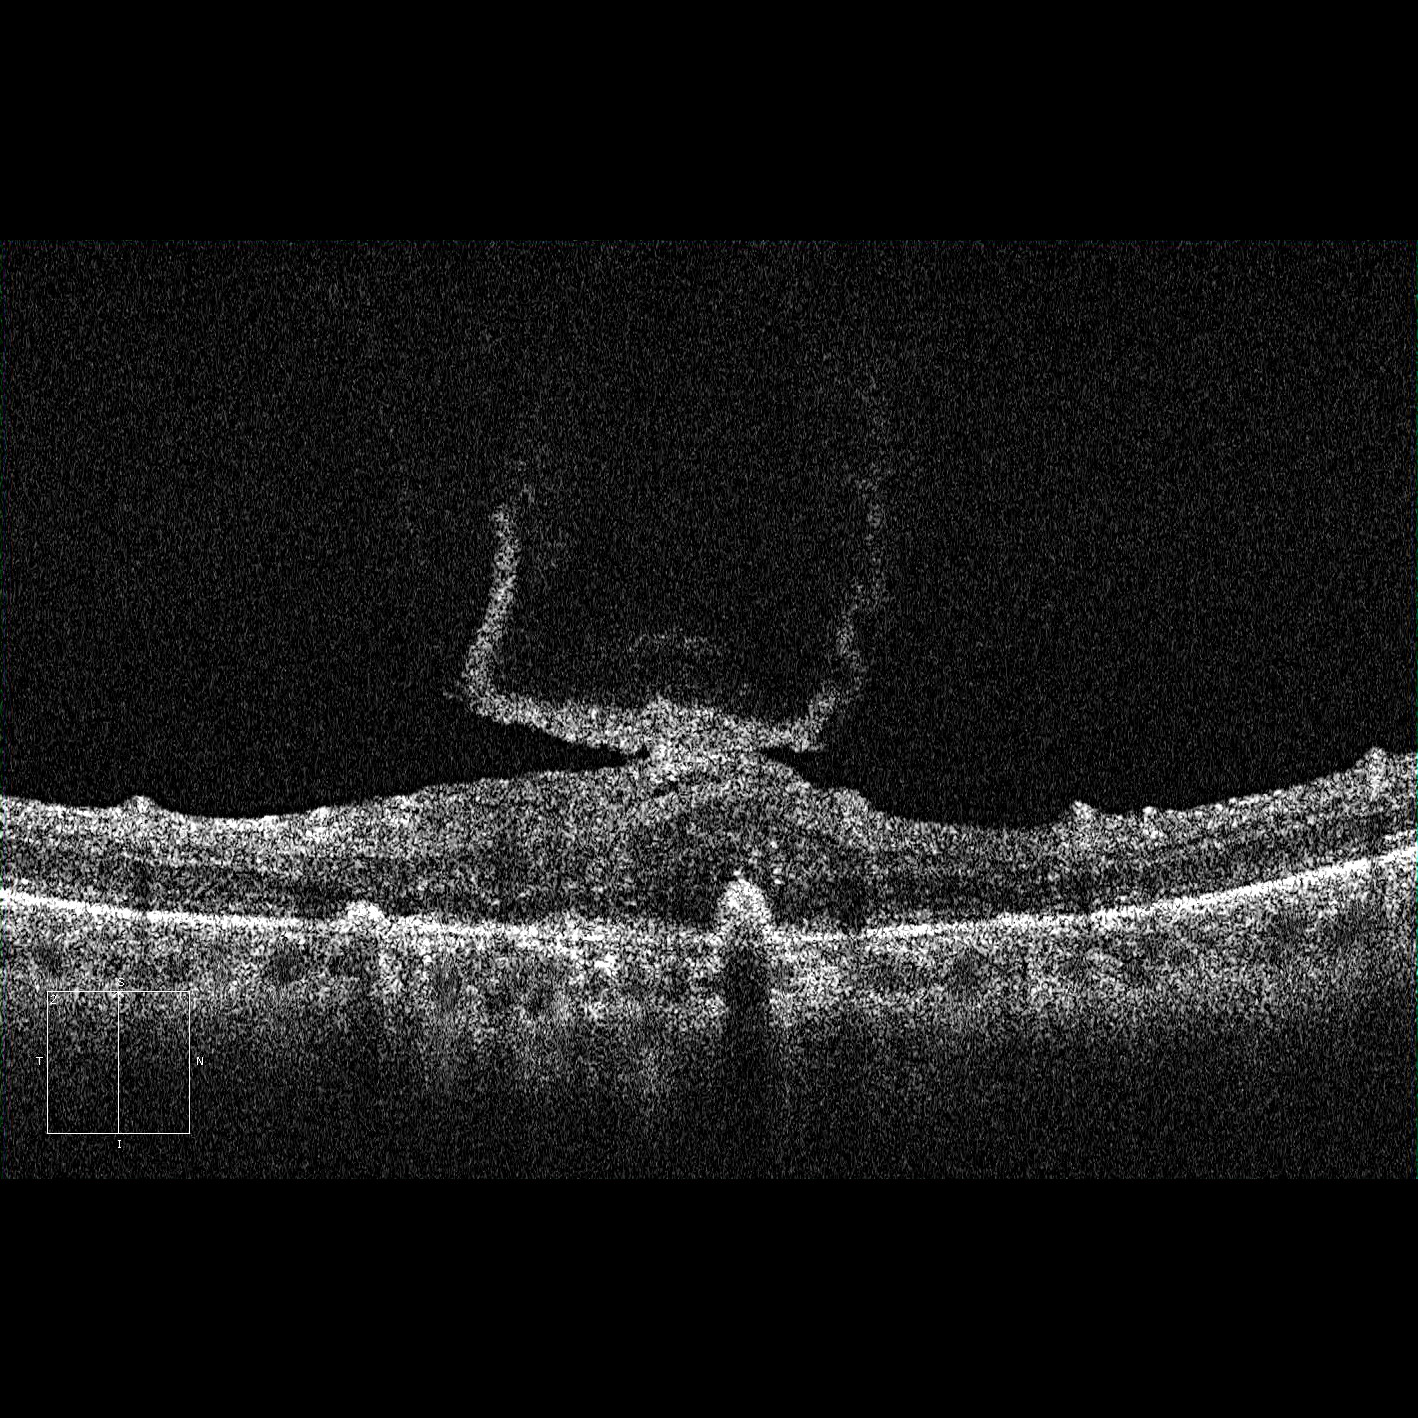

PVD_periph_traction_edited

Full size 1418 × 1418

Published inPVD_periph_traction_edited